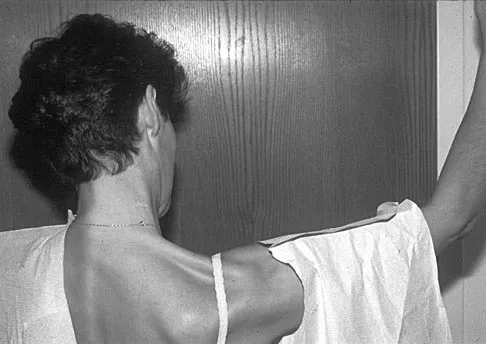

Figure 17 shows the clinical photograph of a 45-year-old female tennis player who has right arm pain and weakness with elevation after undergoing a cervical biopsy several months ago. The cause of her shoulder weakness is damage to the

Explanation

A 45-year-old woman who recently underwent biopsy of a lymph node in the right posterior cervical triangle now finds it difficult to hold objects overhead and has diffuse aching in the right shoulder region. What is the most likely diagnosis?

Explanation